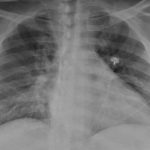

Research: Diabetes, hypertension may increase risk of Coronavirus brain complications

Photo: Chest X-ray of a SARS-CoV-2-positive patient exhibiting confusion and showing weakness on...